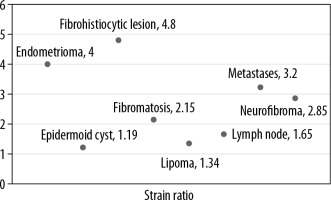

Subsequently, strain elastography was performed to evaluate the size ratio (Figure 3) and strain ratio. Elastography could be performed in 48 lesions; the rest of the lesions were either cystic or vascular in nature. Of these 48 lesions the strain ratio was calculated in all, whereas the size ratio could not be evaluated in 10 lesions due to their larger size in comparison to the probe. The average strain ratio of the lesions in this series was 1.72 ± 0.94 with a wide variability amongst the different pathologies (Figure 4).

The mean strain ratio in epidermoid cysts was 1.19 ± 0.08, which overlapped with that of lipomas (1.34 ± 0.45). The retrospective study by Park et al. found no significant differences between the strain elastography scores of epidermoid cysts and that of other benign tumours [13]. However, the epidermoid cysts were softer than the malignant superficial tumours. Although our study had limited number of cases, the single subcutaneous metastatic lesion we encountered had a strain ratio of 3.2 and that of fibroma and neurofibroma was higher than that of epidermoid cyst at 2.15 ± 0.92 and 2.85 ± 0.54, respectively. However, the significance of this could not be ascertained because it was a single case.

During the duration of this study, we came across a single malignant superficial lesion in the form of a cutaneous metastatic lesion located in the anterior chest wall in a known case of melanoma of the foot (Figure 10). The lesion was hypoechoic and demonstrated a strain ratio of 3.2 on strain elastography. Li et al. found an average strain ratio value of 5.42 ± 3.47 in malignant soft tissue masses, which was higher than that found in benign lesions (1.80 ± 2.10) [21]. Strain ratio > 2.295 and elastic score > 3 was found to be highly sensitive for diagnosing malignant soft tissue tumours (93.8 and 100%, respectively), but the specificity was poor (80.5 and 51.6%, respectively) [21]. However, because we encountered a single case of cutaneous metastatic lesion, calculating the sensitivity and specificity in this context is a limitation of the present study.